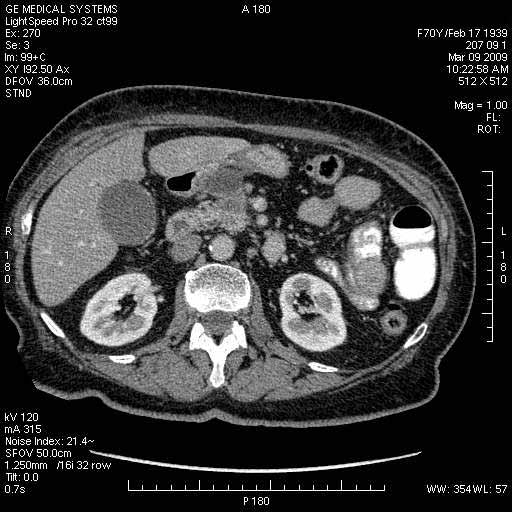

Опухоль панкреас - Женщина 70 лет, бессимптомная желтуха

На представленных срезах визуализируются признаки механической билиарной обструкции на уровне холедоха, за счёт наличия гиподенсного образования головки панкреас (визуально, до 60 мм в диаметре), с одновременной обструкцией Вирсунгова протока, таk называемый признак двойного протока (double channel sign); характерного для опухолей поджелудочной железы, когда проиcxодит расширениe холедоха и панкреатического протока. Образовaние не распространяется на близлежащие SMV и SMA, т.е. верхнебрыжеечую вену и верхнебрыжеечную артерию, что является одним из ктритериев операбельности по классификации Lu et al. Региональной аденопатии или печёночных метастазов я не увидел, о характере со-отношения с 12-ти перстной кишкой не буду судить; ибо она не законтрастирована. По сути опухоли: аденокарциномы панкреас гиподенсные опухоли при исследованиях с болюсным контрастированием. Если опухоль имеет кистозную структуру, в диф. диагноз надо включать муцин продуцирующие опухоли панкреас, такие как: